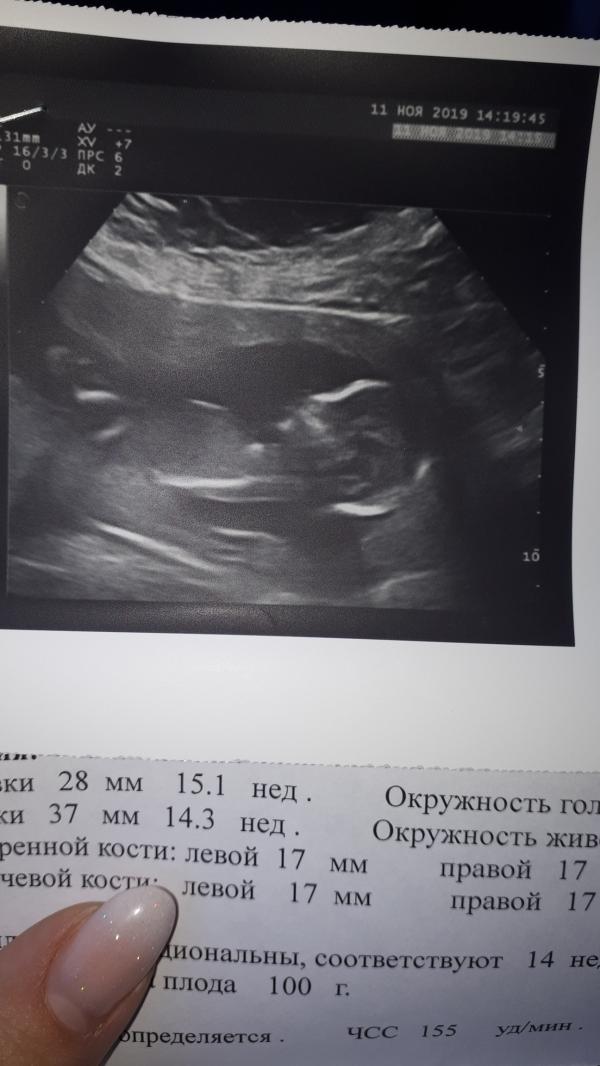

Сходила сегодня на узи. Боже это прелесть,спасибо тебе за этот подарок. Мы весим уже 100 грамм. Мой богатырь,мой мужичок. Расти крепким и здоровым пожалуйста мы тебя с папой и братиком очень любим и очень ждем 😍😍😍.

11.11.2019